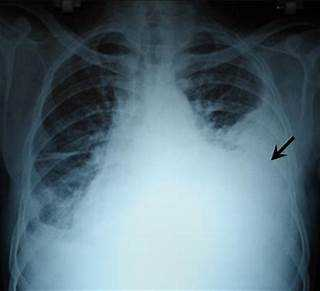

Diminished breath sounds are one of the symptoms that may indicate hemothorax or internal bleeding in a video-assisted thoracic surgery (VATS) patient. VATS is a minimally invasive surgical technique that uses a small video camera (thoracoscope) and special instruments to access the chest cavity through small incisions.

Hemothorax is a condition where blood accumulates in the pleural space, the area between the lungs and the chest wall.

Hemothorax can occur as a complication of VATS due to injury to the lung, blood vessels, or chest wall during the procedure.

Hemothorax can cause compression of the lung and reduce its expansion, leading to diminished breath sounds on the affected side.

Other symptoms of hemothorax may include chest pain, shortness of breath, low blood pressure, rapid heart rate, and pale or clammy skin.

Internal bleeding is another possible complication of VATS that can cause similar symptoms as hemothorax. Internal bleeding can occur due to damage to the major vessels, such as the aorta, pulmonary artery, or vena cava, during VATS. Internal bleeding can cause hypovolemia, which is a decrease in the volume of blood in the body, and hypoxemia, which is a low level of oxygen in the blood. These conditions can impair the delivery of oxygen to the tissues and organs, including the lungs, and cause diminished breath sounds, as well as other signs of shock, such as confusion, weakness, dizziness, and loss of consciousness.

Pain with deep inspiration, bradycardia, and hypertension are not typical symptoms of hemothorax or internal bleeding in a VATS patient. Pain with deep inspiration may be a normal postoperative finding after VATS, as the incisions and the chest tube may cause discomfort. Bradycardia and hypertension may be caused by other factors, such as medications, cardiac disorders, or neurological conditions, but they are not directly related to hemothorax or internal bleeding .